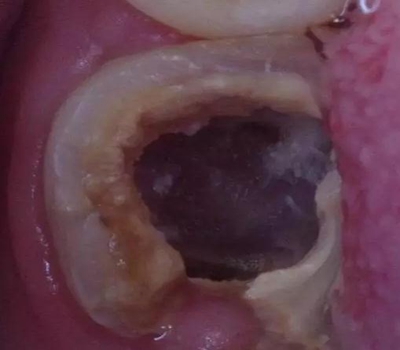

患者:男,23歲,左下六治療過,充填體脫落,慢性牙髓炎癥狀

初診時口內(nèi)照片:

初診時X光片:根分歧炎癥懷疑有底穿,和患者交待病情和費用后開始治療。